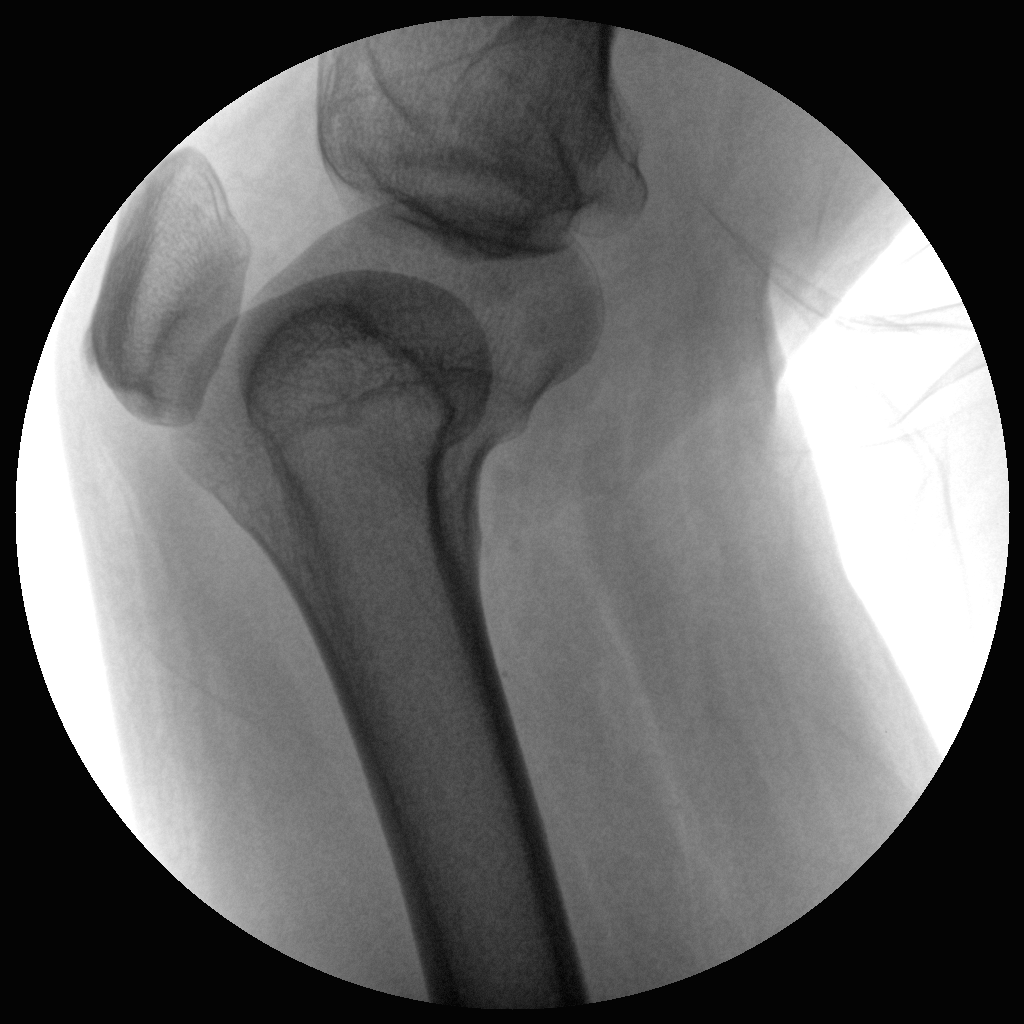

PLX112B 系列高频移动式手术X射线机

●经典影像工作站,可隔室操作避免辐射●全数字化百万像素影像系统,图像清晰●灵活的C臂机架设计,满足临床大范围运动●临床功能丰富,具备脉冲控制、数字摄影、自动透视等●具备手持控制器,远离主机也可自由控制